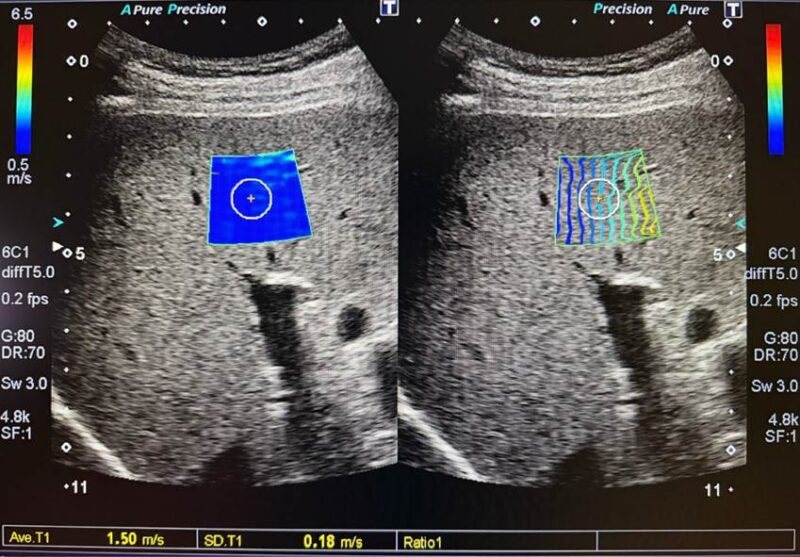

さらに当院では、キヤノンメディカルシステムズ社の超音波診断装置(Aplioシリーズ)を導入しており、通常の腹部エコー検査の一連の流れで「肝硬度測定(Shear Wave エラストグラフィ:SWE)」を行うことが可能です。

【肝硬度測定(エラストグラフィ)とは?】

超音波技術を応用し、肝臓の硬さ(線維化の度合い)をカラーマップと数値で精緻に診断する検査です。検査時間は通常のエコー検査にプラスして2〜3分程度で、事前の絶食など一般的なエコー検査の準備のみで受けていただけます。

【肝硬変への進行リスクを示す数値(m/s)の目安】

組織の硬さをせん断波の伝搬速度(m/s)で表示します。原因疾患(MASHやウイルス性肝炎など)によって多少変動しますが、段階別の一般的な目安は以下の通りです。

- F0〜F1(正常〜軽度): 約 1.3〜1.5m/s 以下

- F2〜F3(中等度〜高度): 約 1.6〜2.1m/s

- F4(肝硬変): 約 2.2m/s 以上

このように、精度の高い装置で「現在の肝臓の硬さ」を数値化して明確に把握することが、適切な治療の第一歩となります。